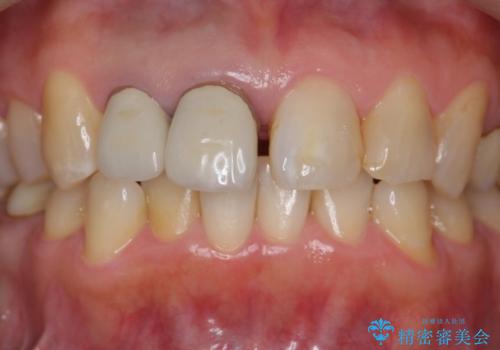

前歯のすき間 以前よりも広がってきた 二度と広がらないようにしたい セラミック治療

- 前歯のすき間を気にして来院。

右上2本を以前セラミックにしたが、前歯のすき間が広がってきてしまったとのこと。

右上の前歯のみの被せなおしですと、右上の前歯が反対側に比べて極端に大きくなってしまうことを説明し、左上の前歯も併せてセラミックにすることにしました。

右上の前歯二本、左上の前歯1本をセラミックにし、正中の前歯を2本連結しました。

気になっていたすき間が閉じて、大変喜んでいただけました。